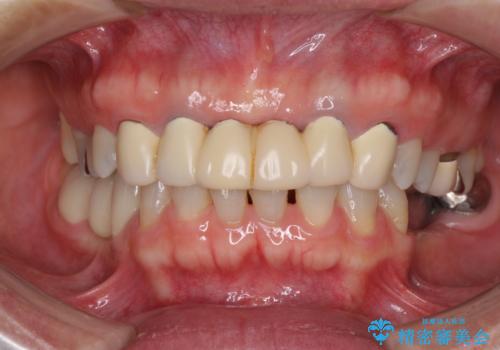

- 口の中に気になるところが沢山あるものの、地元ではなかなか治療を行ってくれるところがないとのことで、沖縄県の離島より来院された患者様です。

金属を使用した前歯のブリッジや奥歯の銀歯は全てオールセラミッククラウンまたはセラミックインレーとし、左下の奥歯はインプラントにより治療を行うこととしました。

外科処置を行うため、治癒を待つ期間が数ヶ月あるため、その期間を利用して下顎前歯のスペースを矯正治療で閉じることとしました。